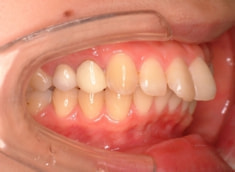

治療後(1年9ヶ月後)

治療開始から1年7ヶ月後